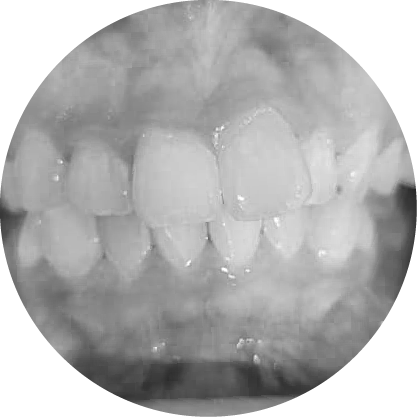

ตัวอย่างในชีวิตจริง